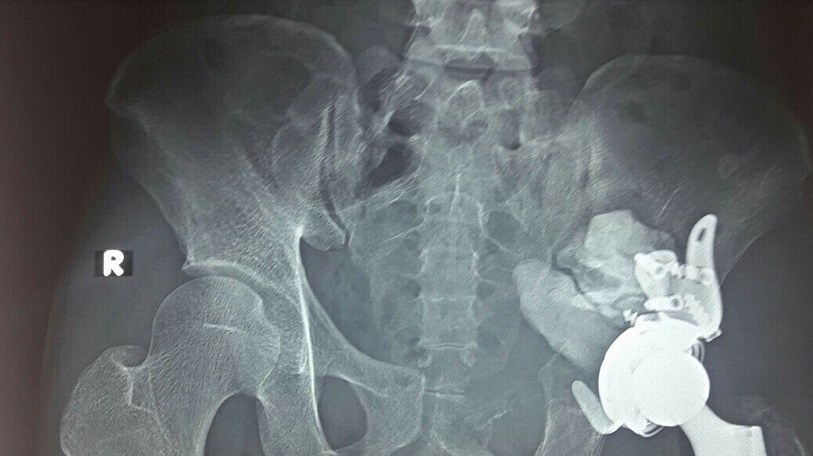

| Khối u vùng ổ cối xương chậu. Ảnh: T.H. |

Sau khi thăm khám và làm các chỉ định cần thiết, các bác sĩ nhận định có một khối u ở vùng ổ cối xương chậu phá hủy gần hoàn toàn ổ cối và phát triển vào ổ bụng bệnh nhân tạo thành một khối đường kính khoảng 10 cm. Kết quả sinh thiết cho thấy bệnh nhân có u tế bào khổng lồ và được chỉ định phẫu thuật. Ca mổ mong muốn lấy bỏ khối u triệt để và tạo hình lại khớp háng giúp bệnh nhân sinh hoạt vận động trở lại.

Cùng với đó, các bác sĩ lựa chọn phương án tạo hình lại khớp háng với khớp háng nhân tạo có sử dụng rọ ổ cối để cố định ổ cối nhân tạo lên cả phần cánh chậu lành. Kíp phẫu thuật kiểm tra kỹ, đặt dẫn lưu và phục hồi giải phẫu của bao khớp và phần mềm.

Sau 6 tiếng đấu trí cam go, ca phẫu thuật đã diễn ra thành công, khối u được lấy bỏ triệt để, không có tai biến tổn thương thần kinh, khớp háng được phục hồi bằng khớp háng nhân tạo giúp cho bệnh nhân có thể tập luyện dần trở lại.